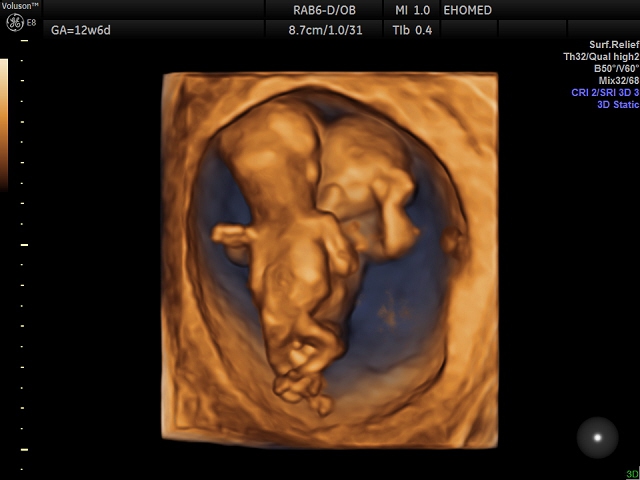

Первый скрининг УЗИ на 13 неделе: Что нужно знать